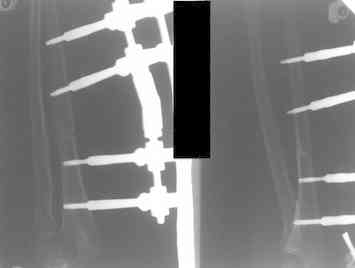

Артротомия, иссечение рубцов, остатков кольцевидной связки. На проксимальный отдел локтевой кости стержневой аппарат (рекомендуют

Compact II выпущеный Stryker Howmedica, но за неименеем...), остеотомия проксимального отдела локтевой кости, вправление головки лучевой кости, замыкание аппарата, проверка стабильности головки

У нас были проблемы. Скорее всего связанные с использованием стержневого аппарата с простым соединением. В Компакте же скорее всего шарнирное, со свободой движения во всех плоскостях, что конечно, значительно должно упрощать фиксацию в правильном положении.

1 подвывих головки лучевой кости в положении супинации - через 2 недели после операции- под ЭОП: аппарат разблокирован, повторное вправление головки, стабилизация аппарата.